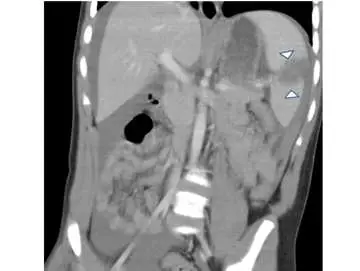

15 歲車禍傷患主訴左上腹部劇痛,而且逐漸呈現休克狀態。電腦斷層檢查如附圖。箭頭所指之異常最符合下列那一項診斷?

本題附圖為腹部冠狀切面(coronal view)的對比增強電腦斷層(contrast-enhanced CT)影像。

- 圖中白色箭頭(arrowheads)指向位於左上腹的**脾臟(spleen)**上極區域

- 脾臟上極可見低密度不規則區域(hypodense irregular area),代表脾臟實質受損、無正常對比增強,符合**撕裂傷(laceration)或血腫(hematoma)**的影像特徵

- 脾臟包膜下或脾周可見血液積聚,與臨床上左上腹疼痛及休克相符

- 肝臟及腸道等其他腹腔臟器無明顯異常,胰臟、腎臟、橫膈無特殊發現

影像定位: 箭頭所指結構位於左上腹腹腔內,位置對應脾臟(第 9-11 肋骨後方),而非胰臟(中線偏左偏後)、腎臟(腹膜後腔)或橫膈(更上方的穹窿狀結構)。